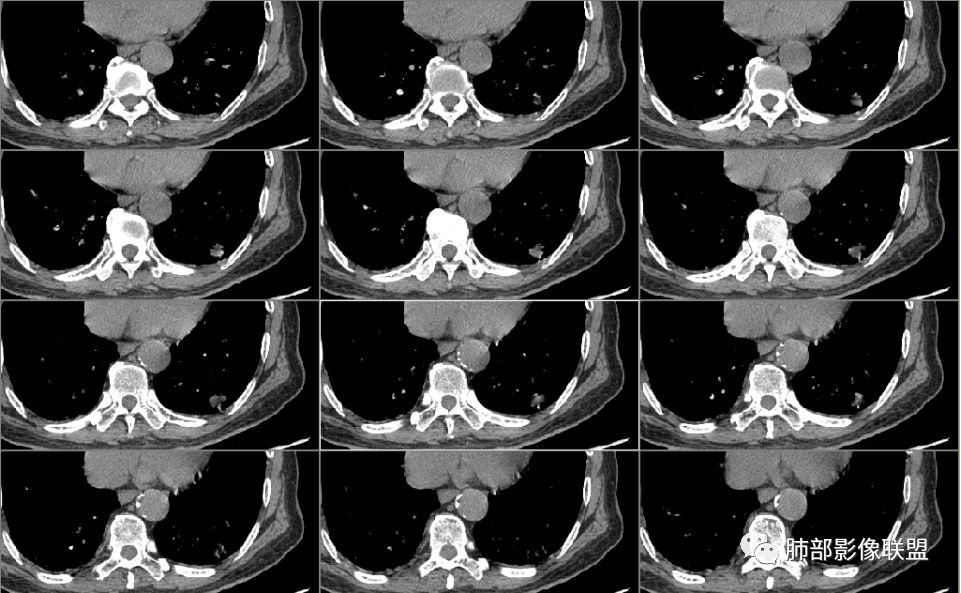

南大分析病例1

南边:

老年男性,因为头部症状来诊,也就是说肺部没症状

胸膜下结节,边界清楚、光滑,边缘稍凹陷,有胸膜牵拉

血管进入?

脐凹?

支气管在门口堵了

一般这类结节,边缘光滑

似有浅分叶

门口支气管堵塞——提示与支气管相关,不支持良性肿瘤

炎性?恶性?

符合炎性的地方:

实性,边缘凹陷,强化均匀

让我们不踏实的地方:

似乎有脐凹征

除了胸膜牵拉,还有短毛刺?血管纠集

支气管在门口堵塞

综合起来看,恶性不能排除。建议穿刺活检,一定要认清楚:我们影像有局限性。

应当说两例患者影像学表现都具有比较明显恶性征象,中老年男性患者,均都没有呼吸系统临床症状。

病例1为胸膜下实性小结节,血管脐凹样出入,可见支气管阻塞。病灶膨隆,部分边缘平直,周围晕征不明显,未见分叶,但可见毛刺及胸膜牵拉,增强后明显强化,老年男性,怀疑新生物尤其是腺癌是有理由的。